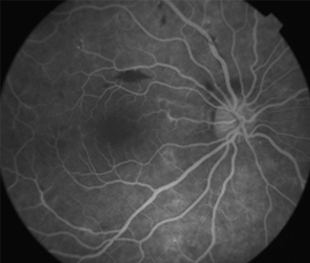

Angiografía OD

- Angiografía: teñido arterial, escape capilar, más tardíamente, no perfusion arteriolar y venular con teñido de las paredes vasculares y dilatación venosa.